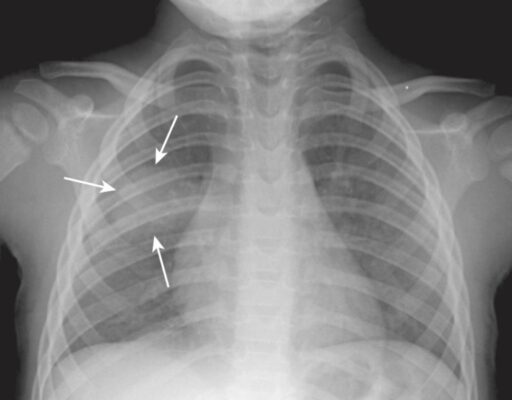

- Một số viêm phổi, chủ yếu ở trẻ em, có thể có hình cầu trên phim chụp X quang phổi.

- Những viêm phổi tròn này hầu như luôn nằm sau phổi, thường là ở các thùy dưới.

- Các tác nhân gây bệnh bao gồm Haemophilus influenzae, Streptococcus và Pneumococcus.

- Viêm phổi tròn có thể bị nhầm lẫn với một khối u ngoại trừ các triệu chứng liên quan đến nhiễm trùng thường đi kèm với các phát hiện ở phổi và các khối u không phổ biến ở trẻ em (Hình 6).